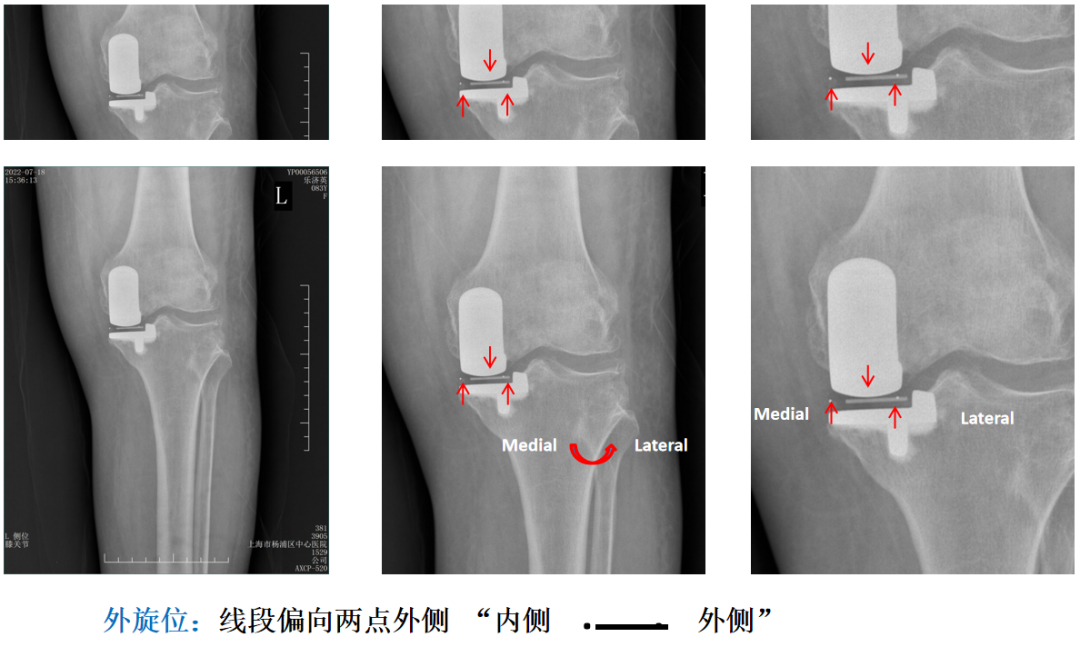

在前后位片(AP),bearing在胫骨底板内外位置通过不透射线“—“和“. ”的标记推断出来。

Bearing的外侧面距离胫骨假体侧壁2-3mm(屈曲位时为1mm,伸直位胫骨发生了外旋)。

辨认bearing内的标识( X-ray正位)

bearing 内的标识:点和线段 “ .—. ” 线段显示为“—”在前;点显示为“.”在后

Bearing 中立位( X-ray正位)

Bearing 内旋( X-ray正位)

Bearing 外旋( X-ray正位)

提示:“ . ”最好在电脑上看